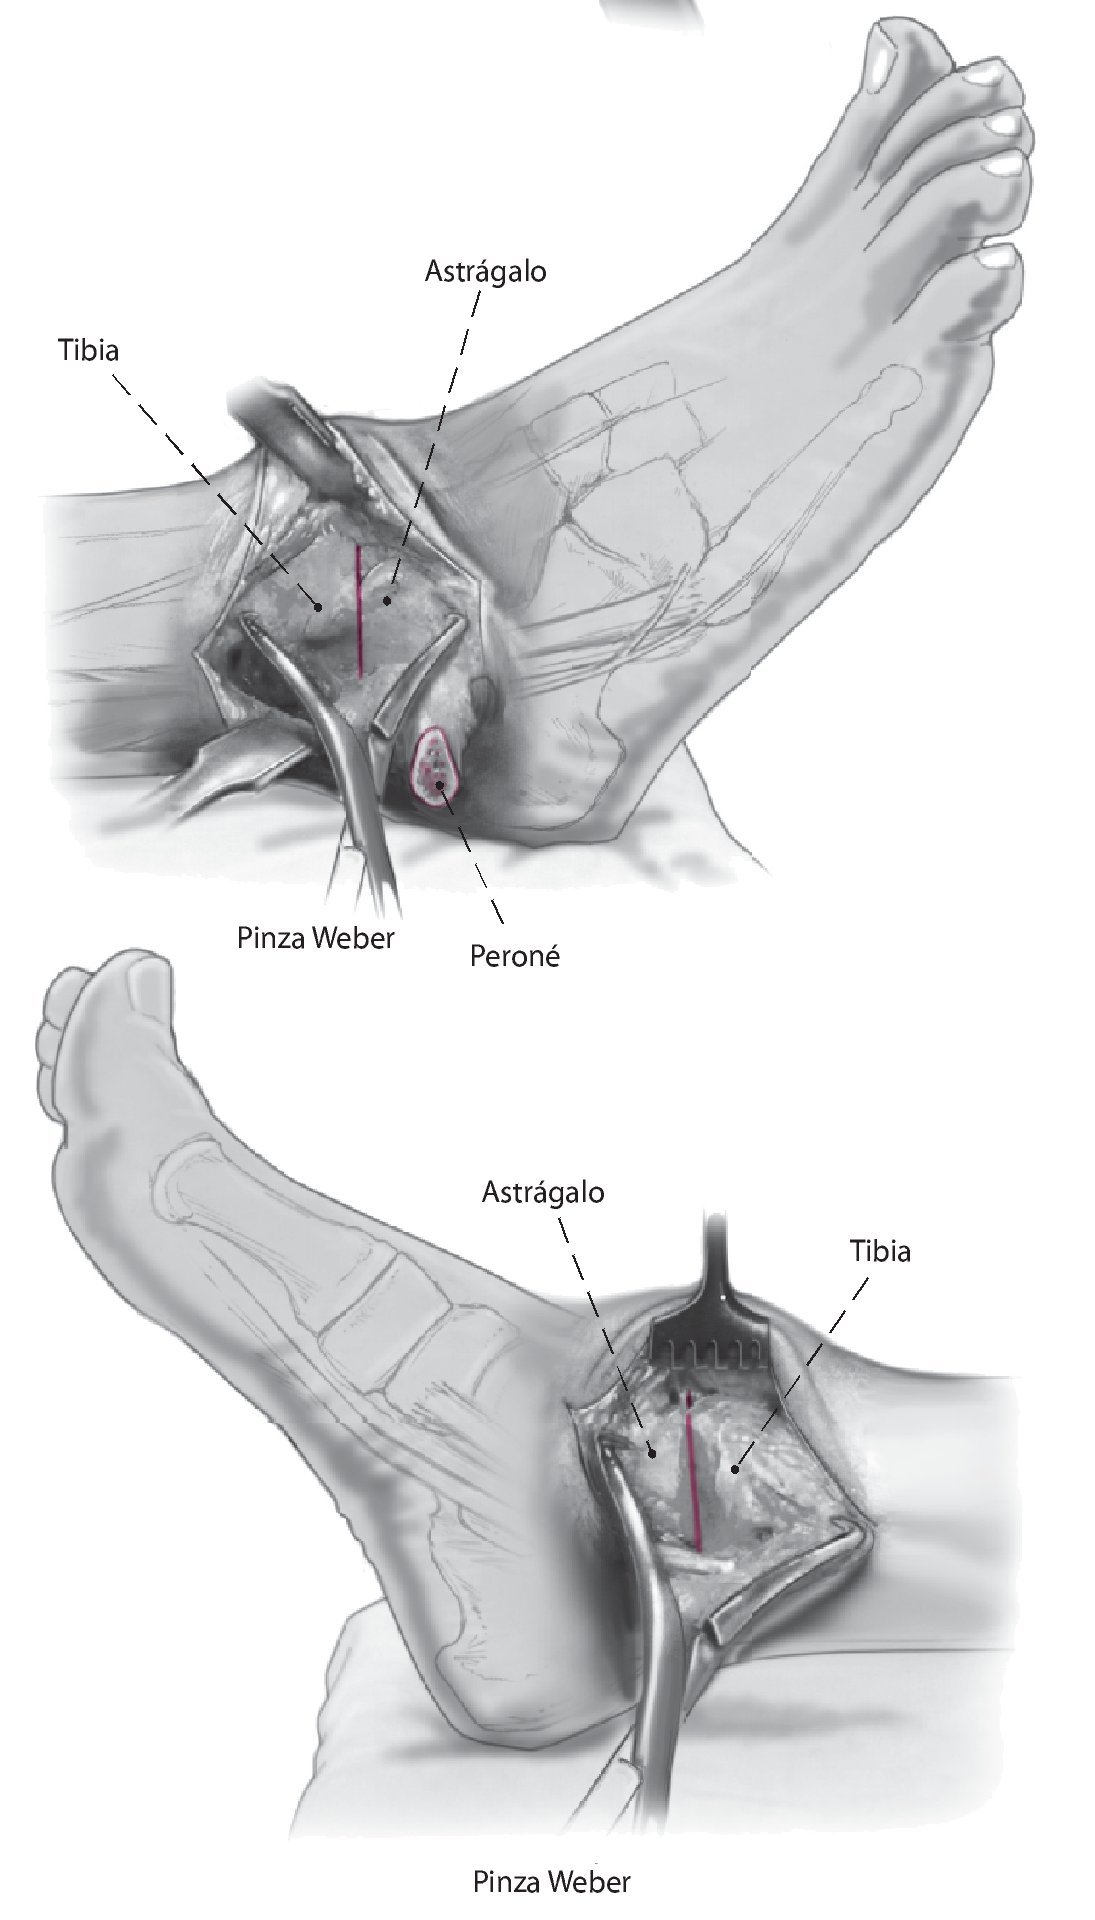

Fig. 9 Compruebe la alineación y aplique fijación provisionalmente con el uso de dos pinzas Weber grandes. Asegurarse de que el astrágalo esté colocado un poco posterior respecto al margen distal de la tibia anterior para reducir así el brazo de palanca anterior del pie.